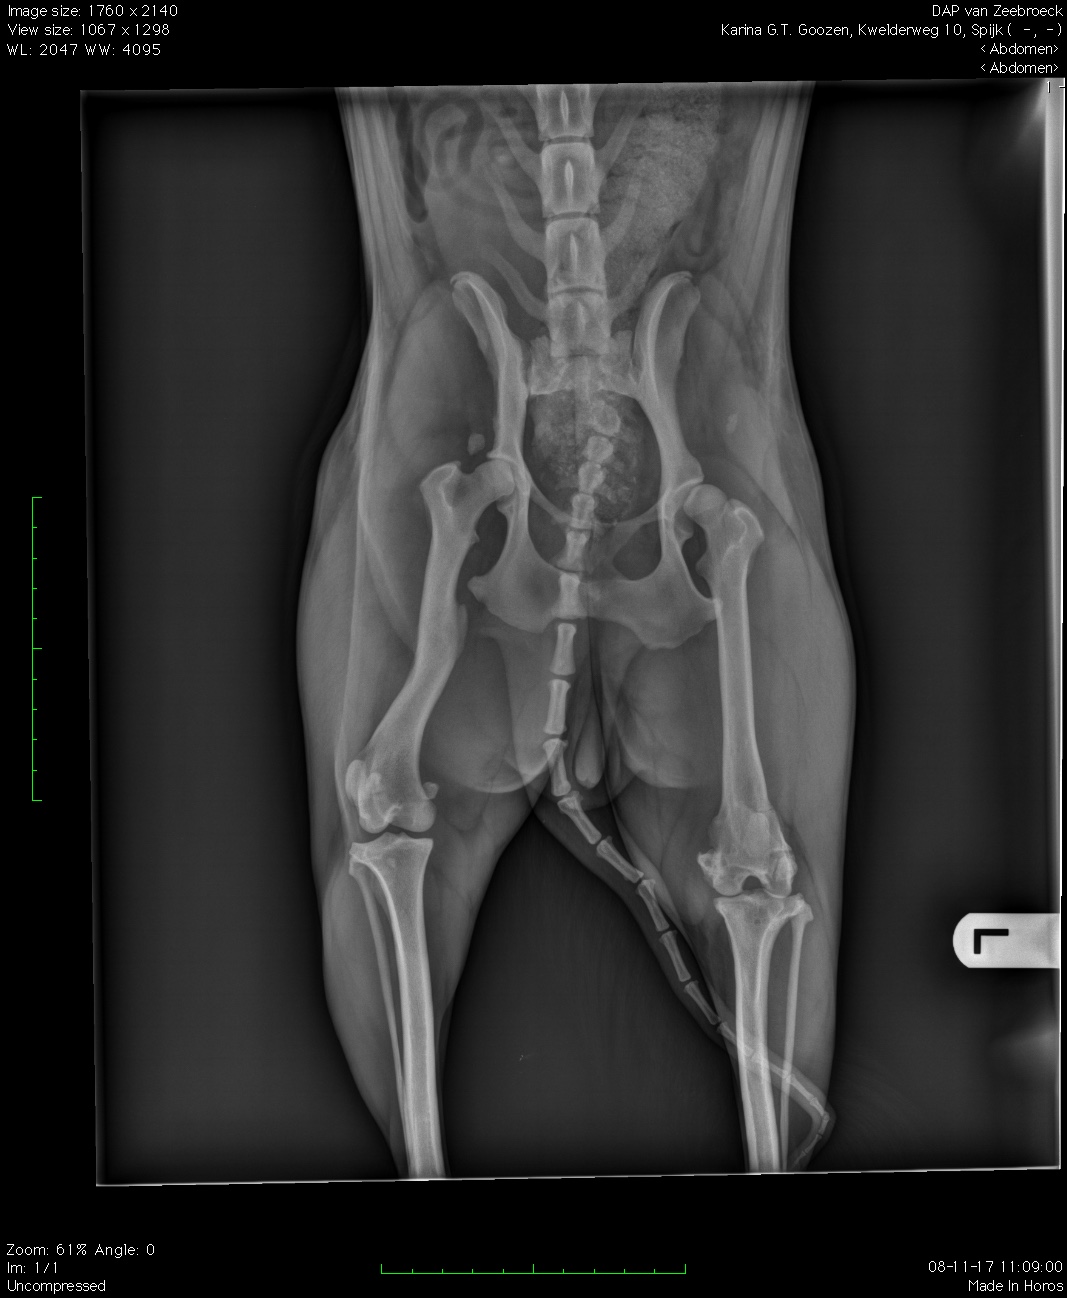

Ik ben Karina, geboren op de straten van Roemenië en ik ben vreselijk mishandeld waardoor ik botbreuken had, die zonder medische verzorging op straat een soort van vast gegroeid zijn. Dagelijks lijd ik nog onder deze foute genezing en heb ik nog steeds vreselijk veel pijn.

Ik had een beetje geluk dat ik in een prive asiel terecht kwam, waar in ieder geval mijn buikje vol was, maar men niet in mij kon kijken en mijn pijn en breuken kon zien. Ik heb de stem niet om het ze te vertellen. Toen mocht ik opeens mee naar een vreemd land met lieve mensen die erg aardig voor mij zijn en een opvangbaasje die heel bezorgd naar me keek en door had dat ik moeilijk liep en mij naar de dokter bracht. Ik was zo blij dat dit opvangbaasje zo goed had gekeken want de dokter zag op de fotos eindelijk dat ik zoveel pijn heb. Ook begrijp ik dat er een dokter is die mij van de pijn af kan helpen maar deze operatie kost ongeveer 2000,00 euro. Stichting DAN, die mij ophaalde en mijn opvangbaasje hebben niet zomaar zo'n groot bedrag en misschien kunnen we allemaal samen een klein beetje betalen, zodat ik snel naar het ziekenhuis kan en eindelijk een verdiend leven krijg zonder elke dag pijn.